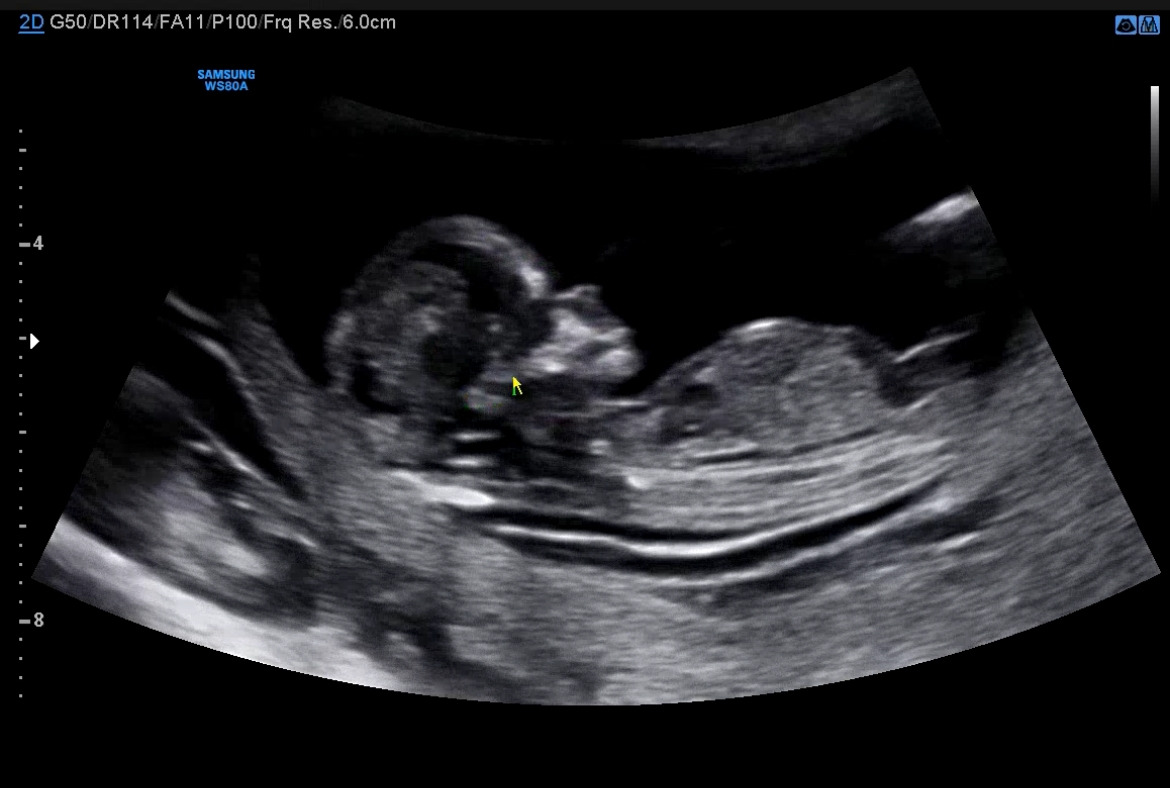

초기 유산 경험이 있던 나는, 늘 유산에 대한 불안감을 가지고 있었다. 아이가 잘 있는지 확인을 하기 위해 거의 14주까지 매주 병원을 방문할 정도였으니까. 그 때마다 아이는 나의 걱정이 무색하게 늘 힘차게 뛰는 심장 소리를 들려주고, 손 발을 귀엽게 꼬물거리며 날 안심시켜주었다.